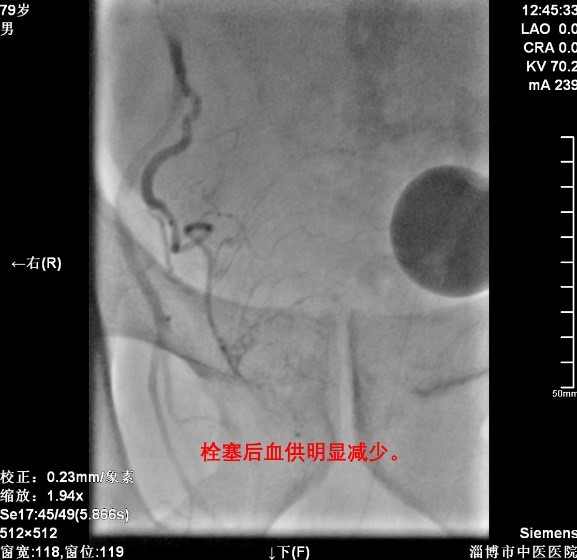

1.患者男,79岁,2021-07-07以“前列腺增生”入院。排尿困难、尿等待,尿频量少,淋漓不尽,长期留置导尿管导尿。外院磁共振示前列腺体积增大,大小约6.3×5.8×6.3cm,前列腺向膀胱突出,膀胱受压。

术后2周复查前列腺超声示前列腺大小约55.7×64.5×46.3mm,体积较术前明显减小。